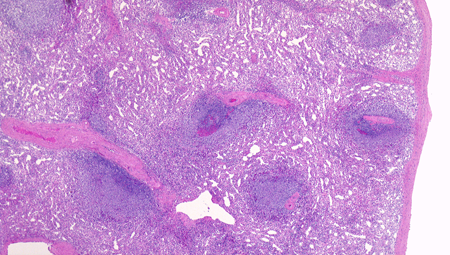

白脾髄の構造

spleenA011.jpg

白脾髄, 辺縁帯/周辺帯は脾臓のリンパ装置として機能する. 開放性末梢血管流床を介して伝達される免疫情報はこれらのリンパ装置で処理され効率よく免疫反応がおこる.

白脾髄 white pulpは中心動脈周囲に形成されているリンパ組織で, 動脈周囲リンパ鞘 periarteriolar lymphoid sheath(PALS)とリンパ濾胞(lymph follicles)の異なる2つの領域が識別される.

脾動脈脾柱という結合組織を通って実質内に入るところから毛細血管に至るところまで、その周囲にリンパ鞘(リンパ鞘=PALS/ peri-arterial lymphatic sheathの略)が形成され、所々にリンパ濾胞が発達している. 濾胞内には胚中心が見られることが多い。胚中心の周りには暗調にそまる小型のリンパ球がマントル層を作って取り囲む。リンパ鞘もリンパ節の構造と同じく粗で不規則な細網線維からできたネットワークが骨格となっている。

リンパ鞘はT細胞領域リンパ濾胞はB細胞由来です。PALSのT-cellsはCD4+ cell > CD8+ T-cells